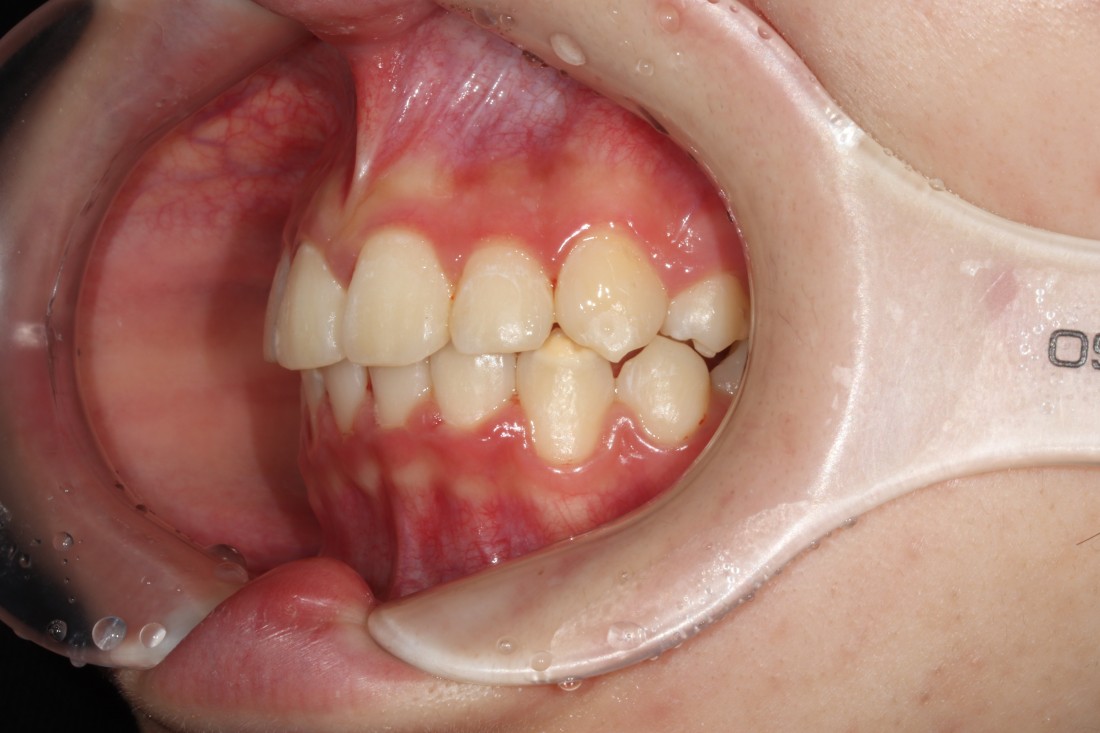

때로는 치아교정만으로 해결하는 것 보다

임플란트 식립을 동시에 해서

더욱 최상의 치료결과를 얻을 수 있을 때가

생기는데요.

20년 경력의 교정전문의 진료와 함께

구강외과 전문의 대표원장님의

협진도 동시에 진행하여

치아교정 기간을 단축하고

성공적으로 고른 치열을 완성하였습니다.